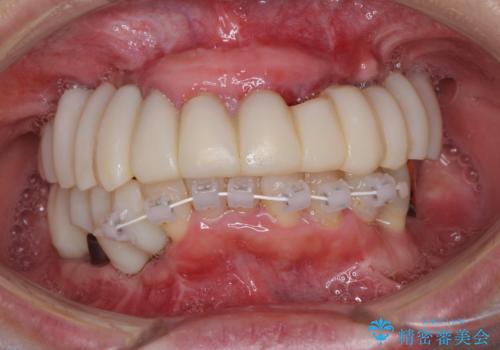

- 歯周病を放置したことで奥歯が抜け、前歯も痛くなってきたとのことで来院された患者様です。

奥歯はほとんどを抜歯しなければならない状態であり、抜歯をせずに済む歯も歯周外科処置や矯正治療を行う必要がある状態でした。

歯を抜かないといけない部分はインプラントとオールセラミッククラウンにより咬合を回復させ、歯周外科処置を行う歯については、同じくオールセラミッククラウンにて補綴治療を行うこととしました。

外科処置を多く行ったため、その待ち時間が長くかかり、さらには途中矯正治療も行なったので、治療期間は長期間となりました。